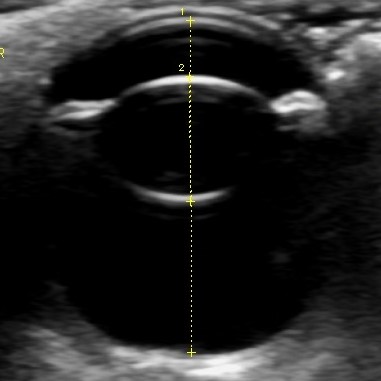

当院では各種眼科検査(涙液量検査・眼圧検査・細隙灯検査・眼底検査・眼超音波検査など)に対応し、一般外来および他の動物病院からの紹介も承っております。